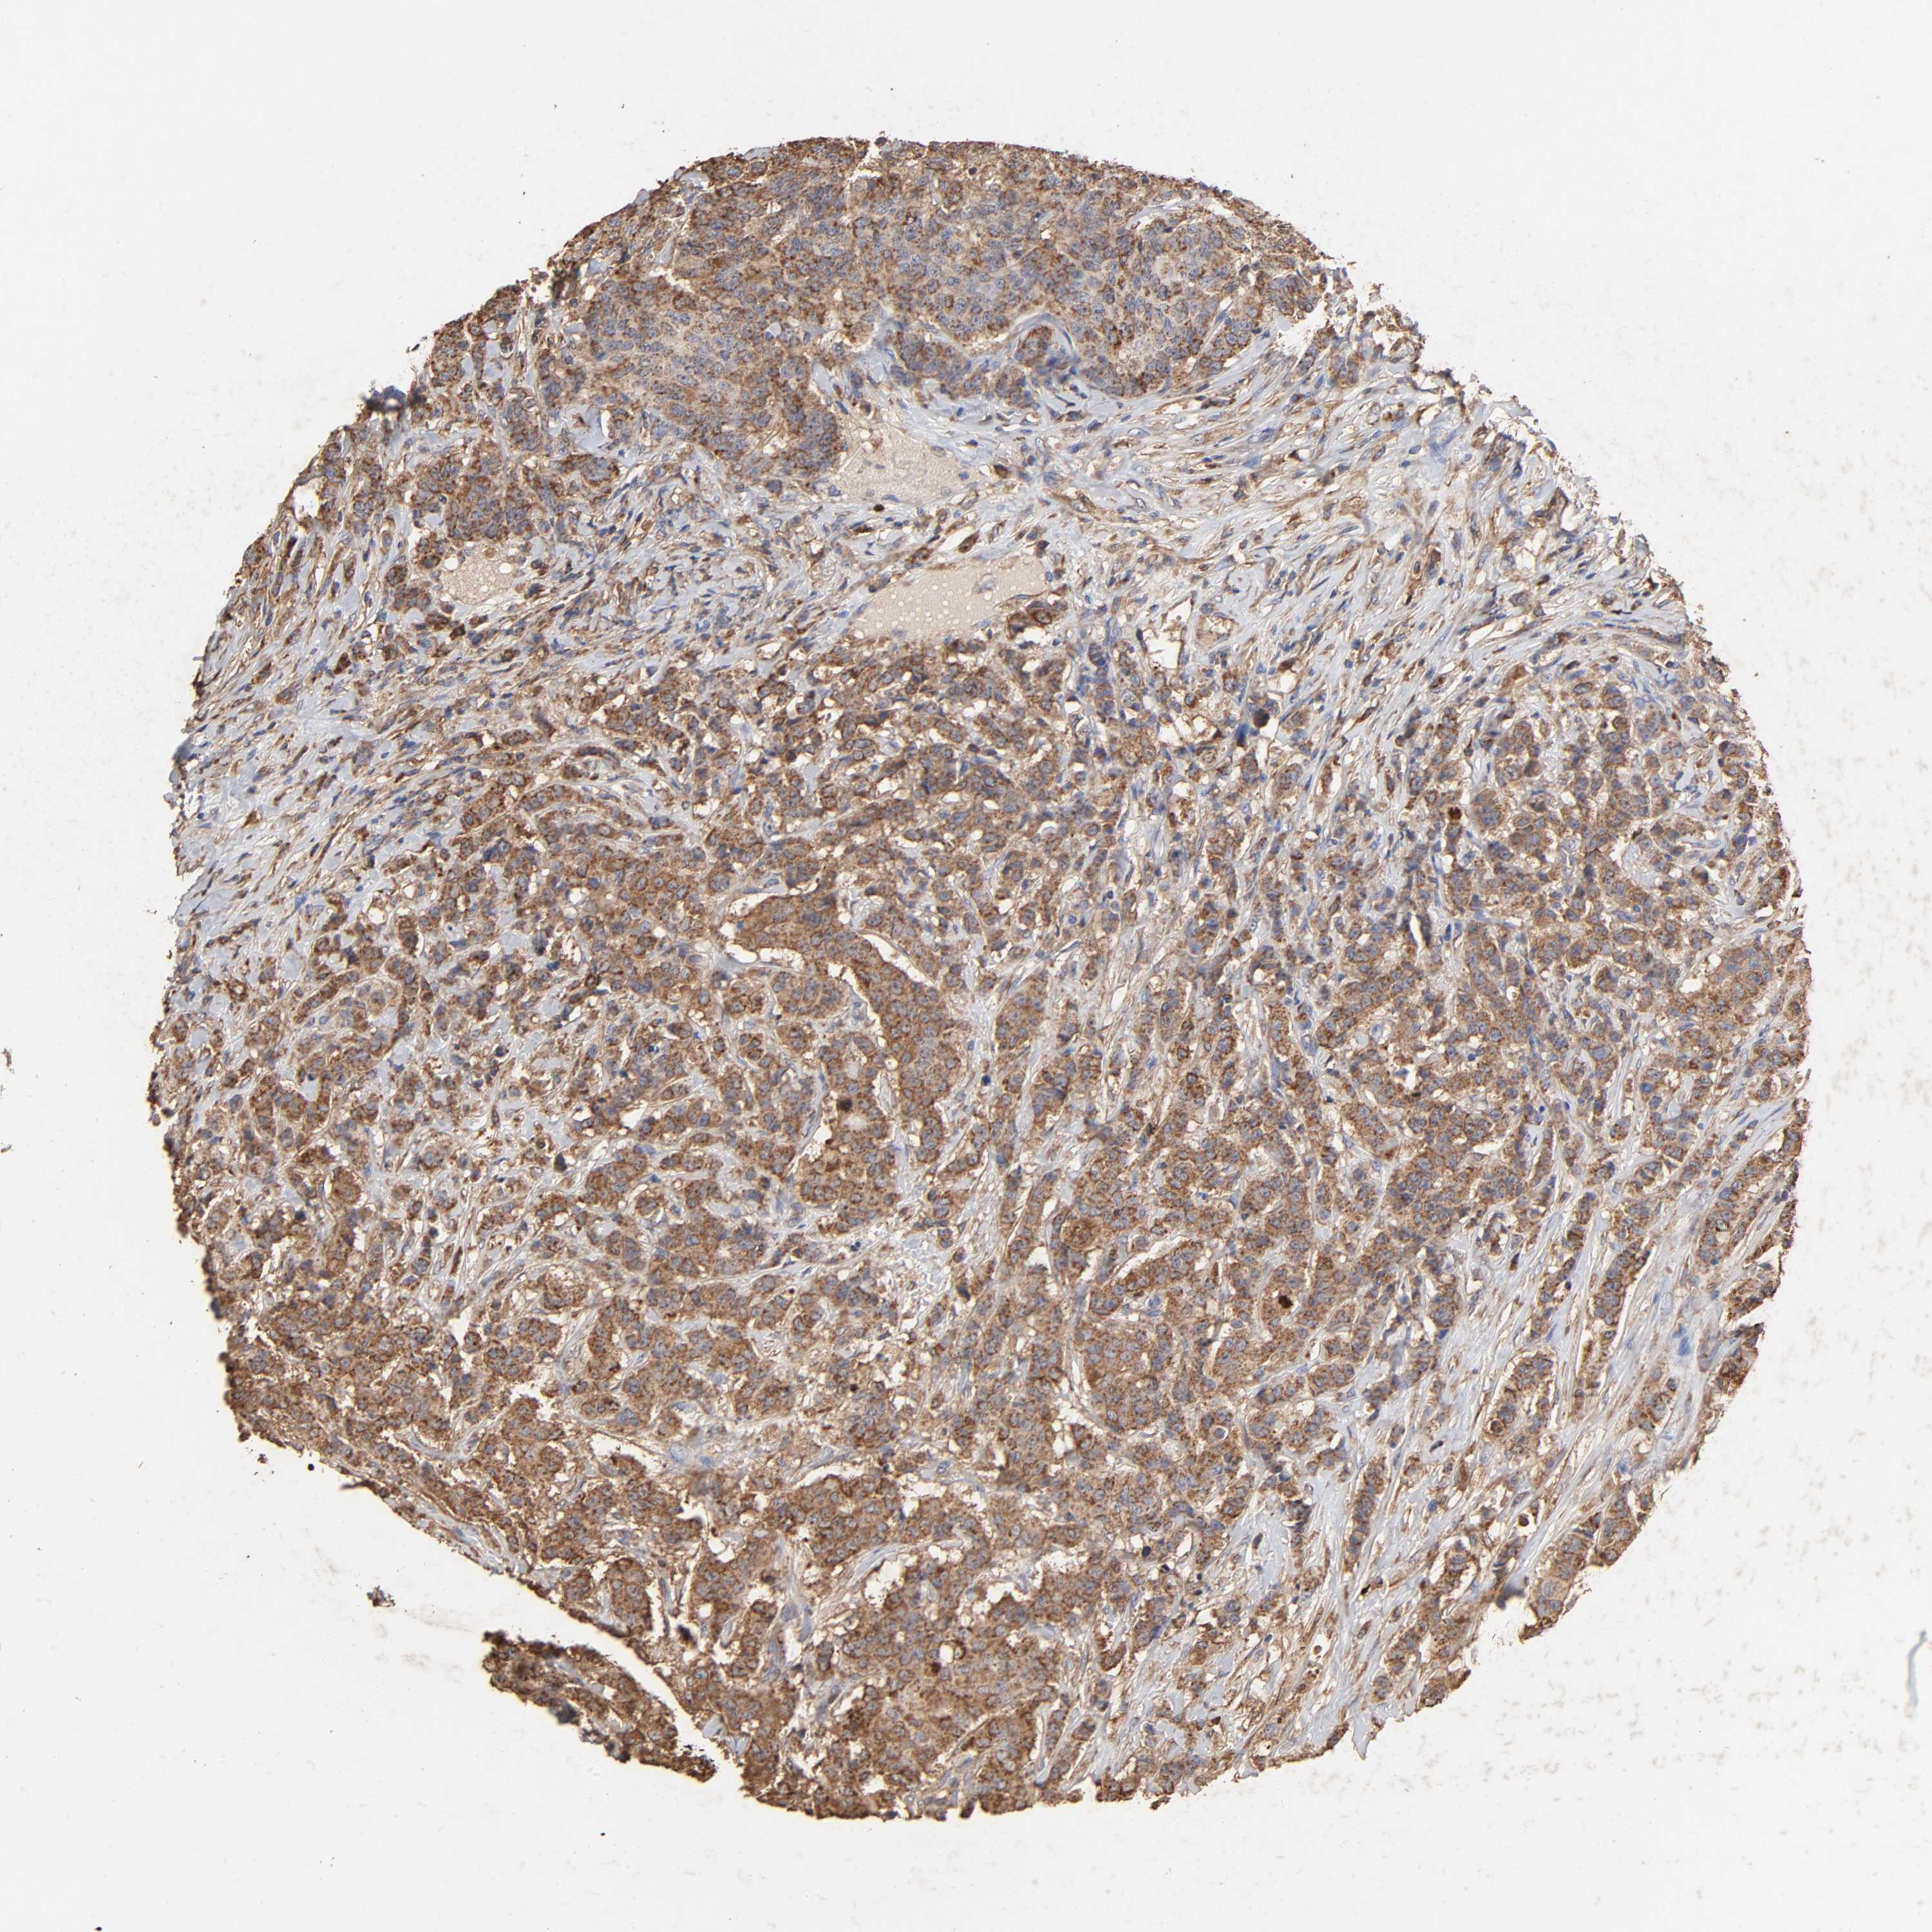

BRCA TCGA BRCA VALIDATION PROTEIN EXPRESSION